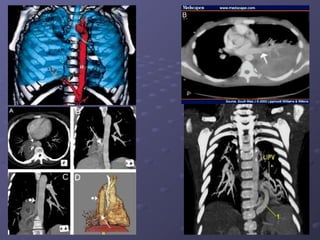

Chụp CT scanner có CQTMChụp CT scanner có CQTM

. Trước tiêm CQ

Sau tiêm CQSau tiêm CQ

Chẩn đoán siêu âm + CTChẩn đoán siêu âm + CT :: bất

thường phổi biệt lập bên trái, có

nhánh động mạch nuôi xuất

phát từ ĐMCN.

- Chụp CT scannerChụp CT scanner (++90%): tiêm cản(++90%): tiêm cản

quang, đa dãy, dựng hình MPR, 3D mạchquang, đa dãy, dựng hình MPR, 3D mạch

máu.máu.

. Là khối choán chỗ đậm độ mô mềm,+_. Là khối choán chỗ đậm độ mô mềm,+_

đồng nhất, ++ cạnh sống trái, +_ dạng ‘tổđồng nhất, ++ cạnh sống trái, +_ dạng ‘tổ

ong’, nang khí or mức khí – dịch. Sau tiêmong’, nang khí or mức khí – dịch. Sau tiêm

cản quang, tăng tỉ trọng không đều, thấycản quang, tăng tỉ trọng không đều, thấy

rõ mạch máu nuôi.rõ mạch máu nuôi.